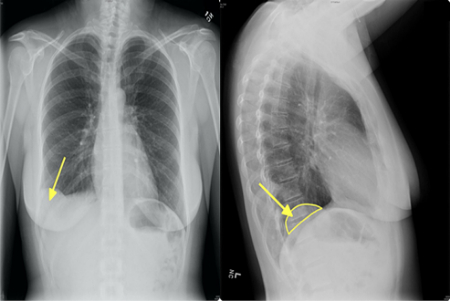

تشخیص

هامارتوماها اغلب به طور اتفاقی در تصویربرداری برای مشکل دیگری کشف می‌شوند. برای تأیید تشخیص ممکن است نیاز به آزمایش‌های تصویربرداری زیر باشد:

• سی‌تی اسکن (CT scan)

• رادیوگرافی (اشعه ایکس)

3. هامارتومای ریه چقدر شایع است؟

شایع‌ترین هامارتومای خوش‌خیم ریه است (حدود ۷۰–۸۰٪ تومورهای خوش‌خیم ریه).

بیشتر در بزرگسالان ۴۰–۶۰ سال دیده می‌شود و در مردان شایع‌تر است.

4. آیا هامارتومای ریه باید عمل شود؟

اگر کوچک باشد و علامتی نداشته باشد → معمولاً فقط پیگیری با سی‌تی اسکن هر ۶–۱۲ ماه. اگر بزرگ‌تر از ۲.۵ سانتی‌متر باشد، در حال تومور باشد یا علائم (سرفه، تنگی نفس) بدهد → جراحی (معمولاً با VATS یا جراحی کم‌تهاجمی).